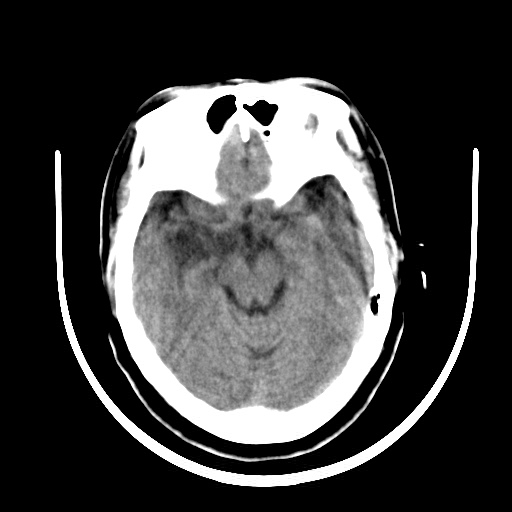

标题: CT16579:女 65岁间断性抽搐. [打印本页]

标题: CT16579:女 65岁间断性抽搐.

考虑右侧颞叶脑软化灶并脑穿通畸形;建议必要时行进一步检查。

右侧蛛网膜囊肿

右颞叶脑软化灶。余未见明显异常。

右颞叶软化灶,右基底节区腔隙性脑梗塞;